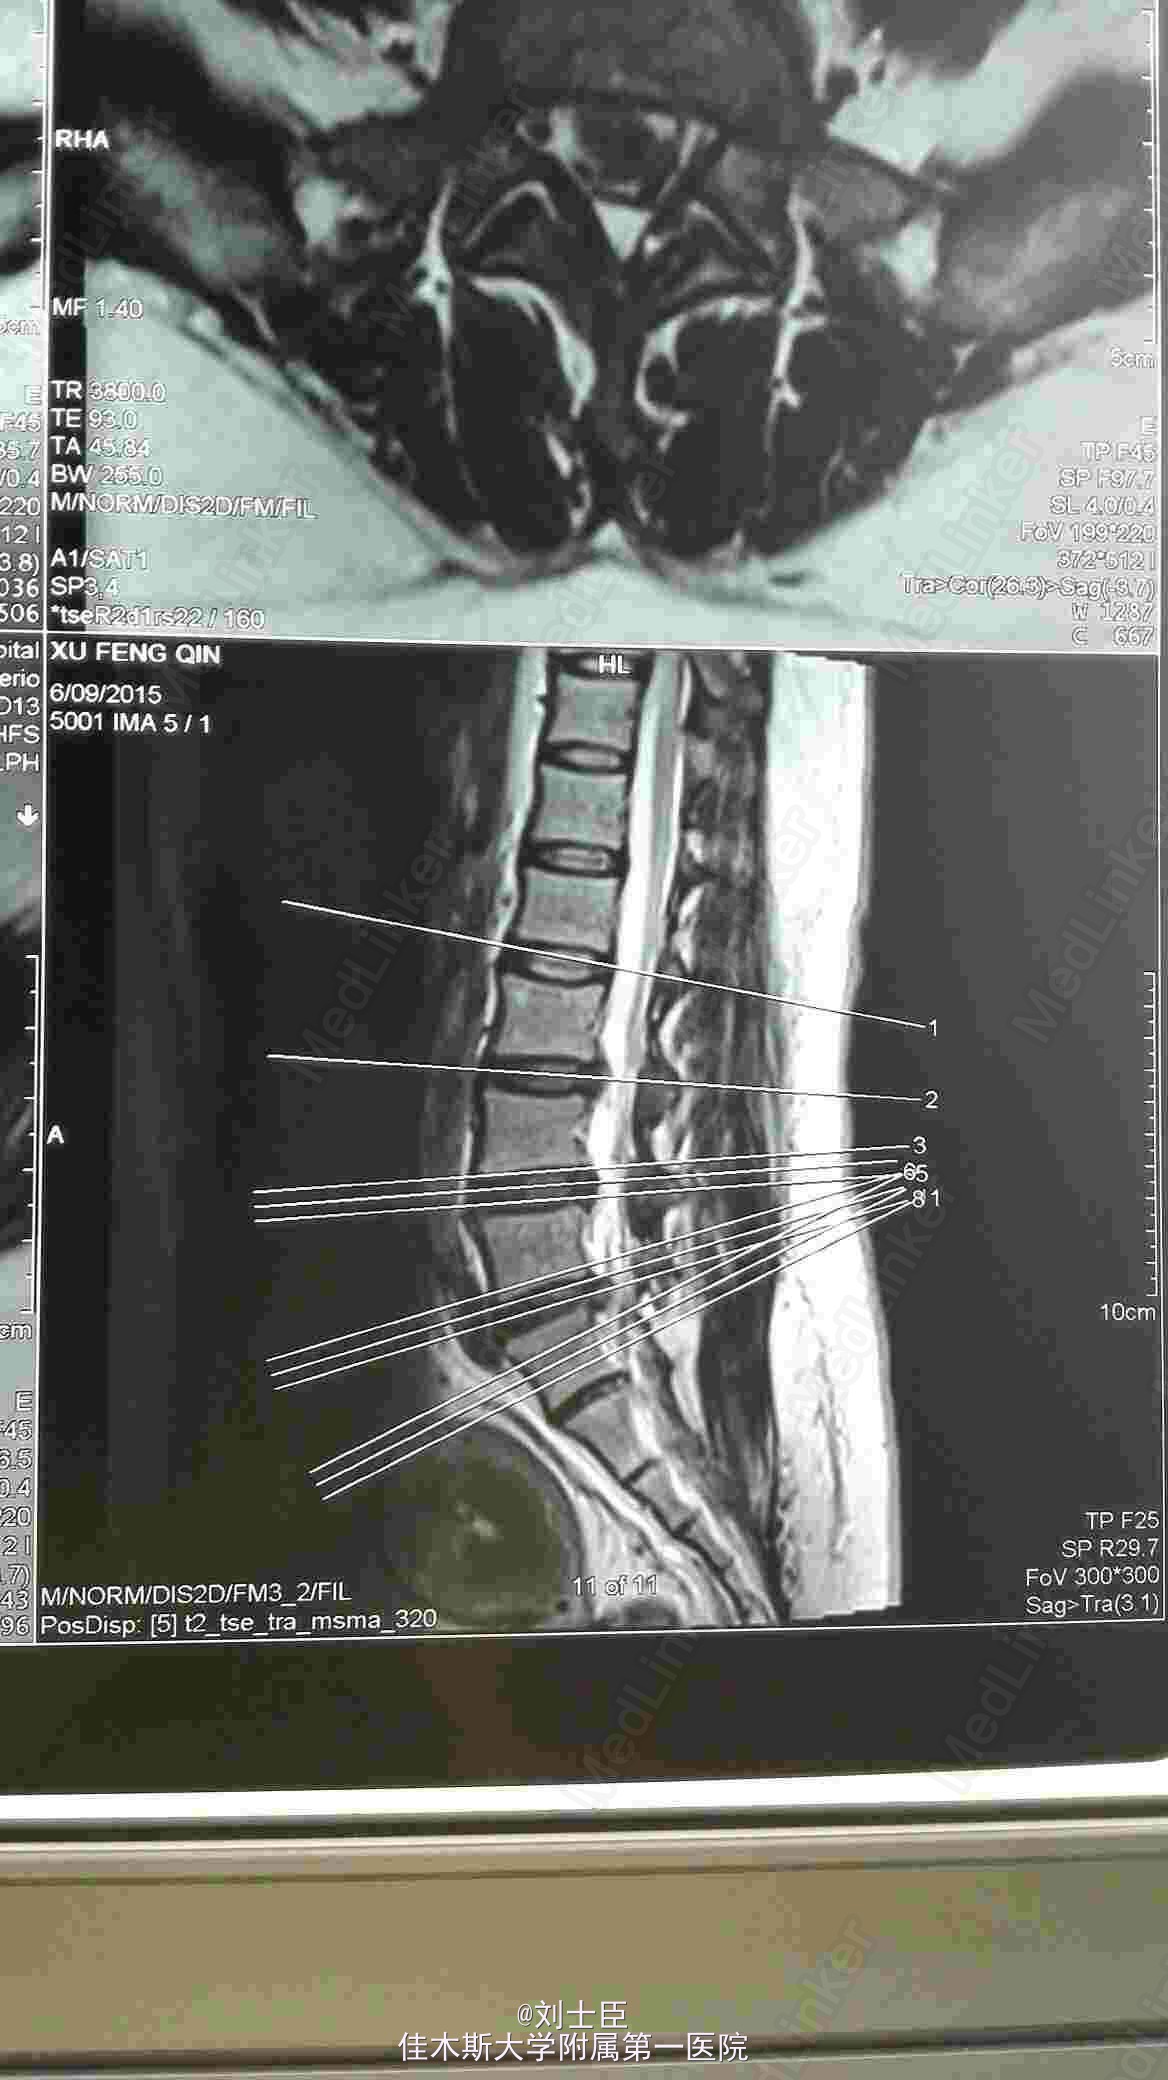

打开应用巨大游离间盘怎么治?

某某,女,43岁。腰痛伴双下肢疼痛1年伴二便失禁7天。

腰5骶1间盘突出症。马尾综合征。椎间孔镜下游离间盘摘除术纤维环成形术。

病人术后即可刻下地行走自如,直腿抬高实验阴性。3天后拔出尿管,二便正常,双下肢和臀区感觉麻木减轻。

针对以往腰椎间盘突出症大都切开手术,创伤大,恢复慢,并发症多,复发后再手术困难。应用椎间孔镜完全可以治愈间盘突出症,达到创伤小,破坏小,恢复快,痛苦少,针对一个病处可反复手术。